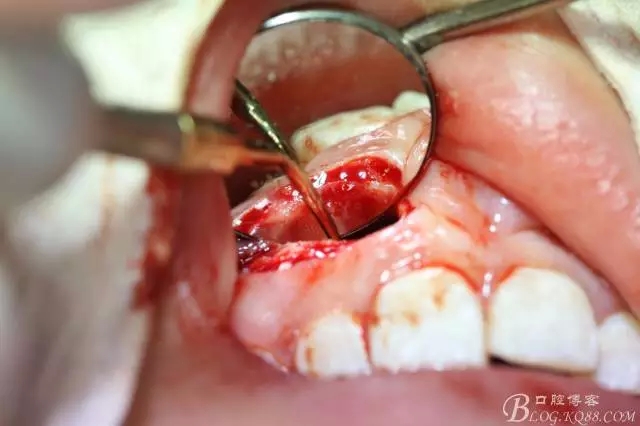

病例資料: 患者、柴xx、女、16歲。專科檢查及病歷如下圖: 患者同意我院正畸科建議,遂轉(zhuǎn)診倒外科。術(shù)前簽知情同意書。 治療過程: 圖1.術(shù)前的CBCT檢查:13阻生,疑為含牙囊腫。縱剖面顯示12牙根吸收至根尖1/3。 圖2.局部麻醉下 。行唇側(cè)弧形切口,12松動不到1°。 圖3.翻瓣、暴露骨面。 圖4.去骨、 暴露13牙冠 圖5.去骨、逐漸顯露13。 圖7.拔除13. 圖8.摘除囊壁 圖9.必須完整剝離囊壁。 圖10.摘除囊壁后形成的骨腔 圖11.超聲骨刀12根尖倒預(yù)備 圖13. 消毒棉球骨腔內(nèi)隔濕血液,紙尖干燥倒預(yù)備好的根管 圖14. 紙尖無血即可 圖15。MTA倒充填 圖16.骨腔填塞膠原蛋白海綿 圖17.拔除的13及摘除的囊壁 圖18.縫合 圖19.術(shù)后x線根尖片影像:MTA封閉根尖